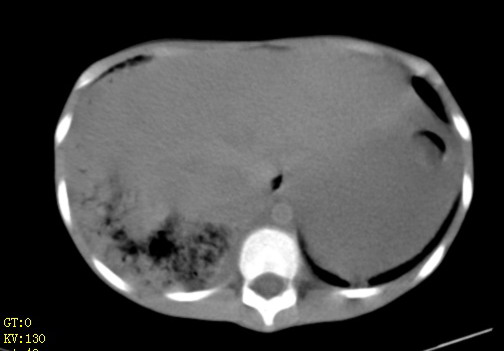

女,12岁,气促、咳嗽2天,3个月前查胸片示:两肺感染,急诊入院查ct,血常规等未检查。

双肺中下野不规则片絮状阴影,中外带明显,双侧胸腔少量积液,心影增大,心腔密度减低,隆突下及左侧气管旁见钙化淋巴结影,考虑双肺感染、心衰;建议结合临床除外h1n1并急性心衰,先心不能排除。

两肺多发片絮状模糊影,以下肺外带居多,内见支气管气像,纵膈窗未减影,两侧胸腔积液,心影增大,结合心超,支持重症肺炎,非常时期,甲型h1n1流感不排除。